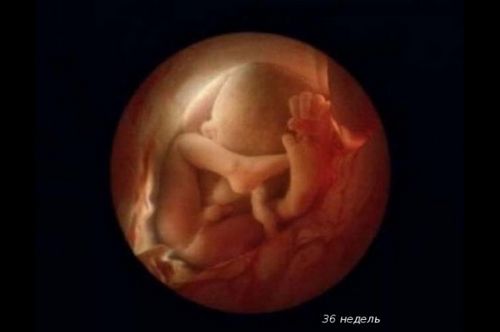

З 28 тижня легені плоду готові дихати звичайним повітрям. Всі його органи сформовані, тепер малюкові залишилося активно рости і додавати у вазі.

Малюк вміє плакати і відповідає, найчастіше стусанами :), на зовнішні звуки. Чітко простежуються його біоритми: під час неспання дитина відкриває очі і закриває, коли спить.

Вага дитинки складає в середньому 2,500 кг. Довжина малюка - 47 см.

З цього часу плід вважається зрілим і готовий до народження. Він з нетерпінням чекаємо зустрічі з вами!